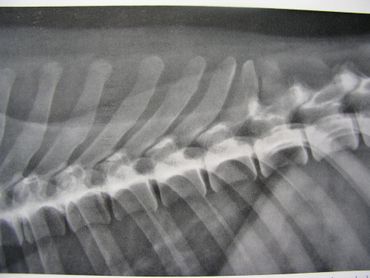

The spinal column is made up of four major vertebral regions: cervical (neck), thoracic (mid back), lumbar (low back) and sacral (pelvic). Dogs have seven cervical, thirteen thoracic, seven lumbar and three sacral vertebrae. There are also variable numbers of coccygeal or tail vertebrae. Intervertebral disks are located between the vertebral bodies starting at the second and third cervical vertebrae (C2-3) and extending to the seventh lumbar and first sacral vertebrae (L7-S1). The three sacral vertebrae are fused and therefore do not have disks. Intervertebral disks are present between the coccygeal vertebra as well, but are of little clinical significance.

The canine spinal anatomy is very similar to us humans, with the exception of 1 additional thoracic vertebra and 2 additional lumbar vertebra...